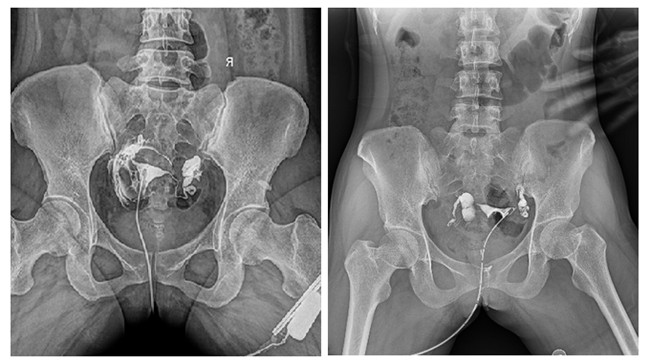

相较于传统胃肠机,动态DR矩形采集面积大,一次曝光即可显示整个盆腔,大幅减少观察时间,可控的瞬时照射避免受检者吸收过多的X线,对育龄期女性的检查尤为重要。毫秒级时间内高清点片,可以在造影剂流动的过程中完成拍片,抓拍到关键图像,更加清楚地了解到管腔的具体通畅情况及堵塞部位,对检查及诊断有非常重要的价值。

此外,应用平板动态DR进行子宫输卵管造影,还可以在加压推注下,使部分输卵管轻、中度堵塞的患者得以通畅,起到一定的治疗作用。

平板动态DR依托于可视化点片以及超大高清幅面等先进功能,可应用于多种不孕等妇科检查。目前在国内外医疗机构中,使用动态DR进行子宫输卵管造影是检查子宫输卵管炎的主要方法,同时还有分离粘连的治疗作用,一举两得。不可否认,多功能动态DR的出现,使得妇科造影检查水平得以进一步提高。